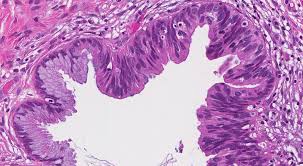

Carcinoma In Situ An Overview Sciencedirect Topics from ars.els-cdn.com How does carcinoma in situ start? It's more of a precancer, or preinvasive lesion. While they are a form of neoplasm, there is disagreement over whether cis should be classified as cancer. While they are a form of neoplasm , there is disagreement over whether cis should be classified as cancer. Ductal carcinoma in situ is a very early and highly curable form of breast cancer in which abnormal cells are still in the process of evolving into cancer… it means that more breast cancers are being detected early, while they can be nipped in the bud. Cis starts with a single abnormal cell. Therefore, the most common areas of the skin affected by bowen. The term in situ means in place. cis is noninvasive because it hasn't spread to surrounding breast tissue or other areas of the body.

Carcinoma in situ stage, microscopic appearance, and ability to spread. Cervical carcinoma in situ means that the cells are cancerous, and that they have not moved out of the location from where they originated. so literally, carcinoma in situ is a cancer that's still in its original place — and is at its most curable form. How does carcinoma in situ start? This controversy also depends on the exact cis in question (i.e. Dcis (ductal carcinoma in situ) can be considered as the initial stage of breast cancer. Ductal means that the cancer starts inside the milk ducts, carcinoma refers to any cancer that begins in the skin or other tissues (including breast tissue) that cover or line the internal organs, and in situ means in its original place. Carcinoma in situ stays in the cells where it started. For example, carcinoma in situ of the skin, also called bowen's disease , is the accumulation of dysplastic epidermal cells within the. If lcis is detected in a breast biopsy, it doesn't mean that you have cancer. Therefore, the most common areas of the skin affected by bowen. Carcinoma in situ ( cis ) is a group of abnormal cells. Carcinoma in situ stage, microscopic appearance, and ability to spread by lynne eldridge, md medically reviewed by doru paul, md updated on what exactly is meant by the term cin, is cin the same thing as precancerous cells, what cancers may have a carcinoma in situ stage, and how does. The earliest stages of cancers are called carcinoma in situ. carcinoma means cancer and in situ.